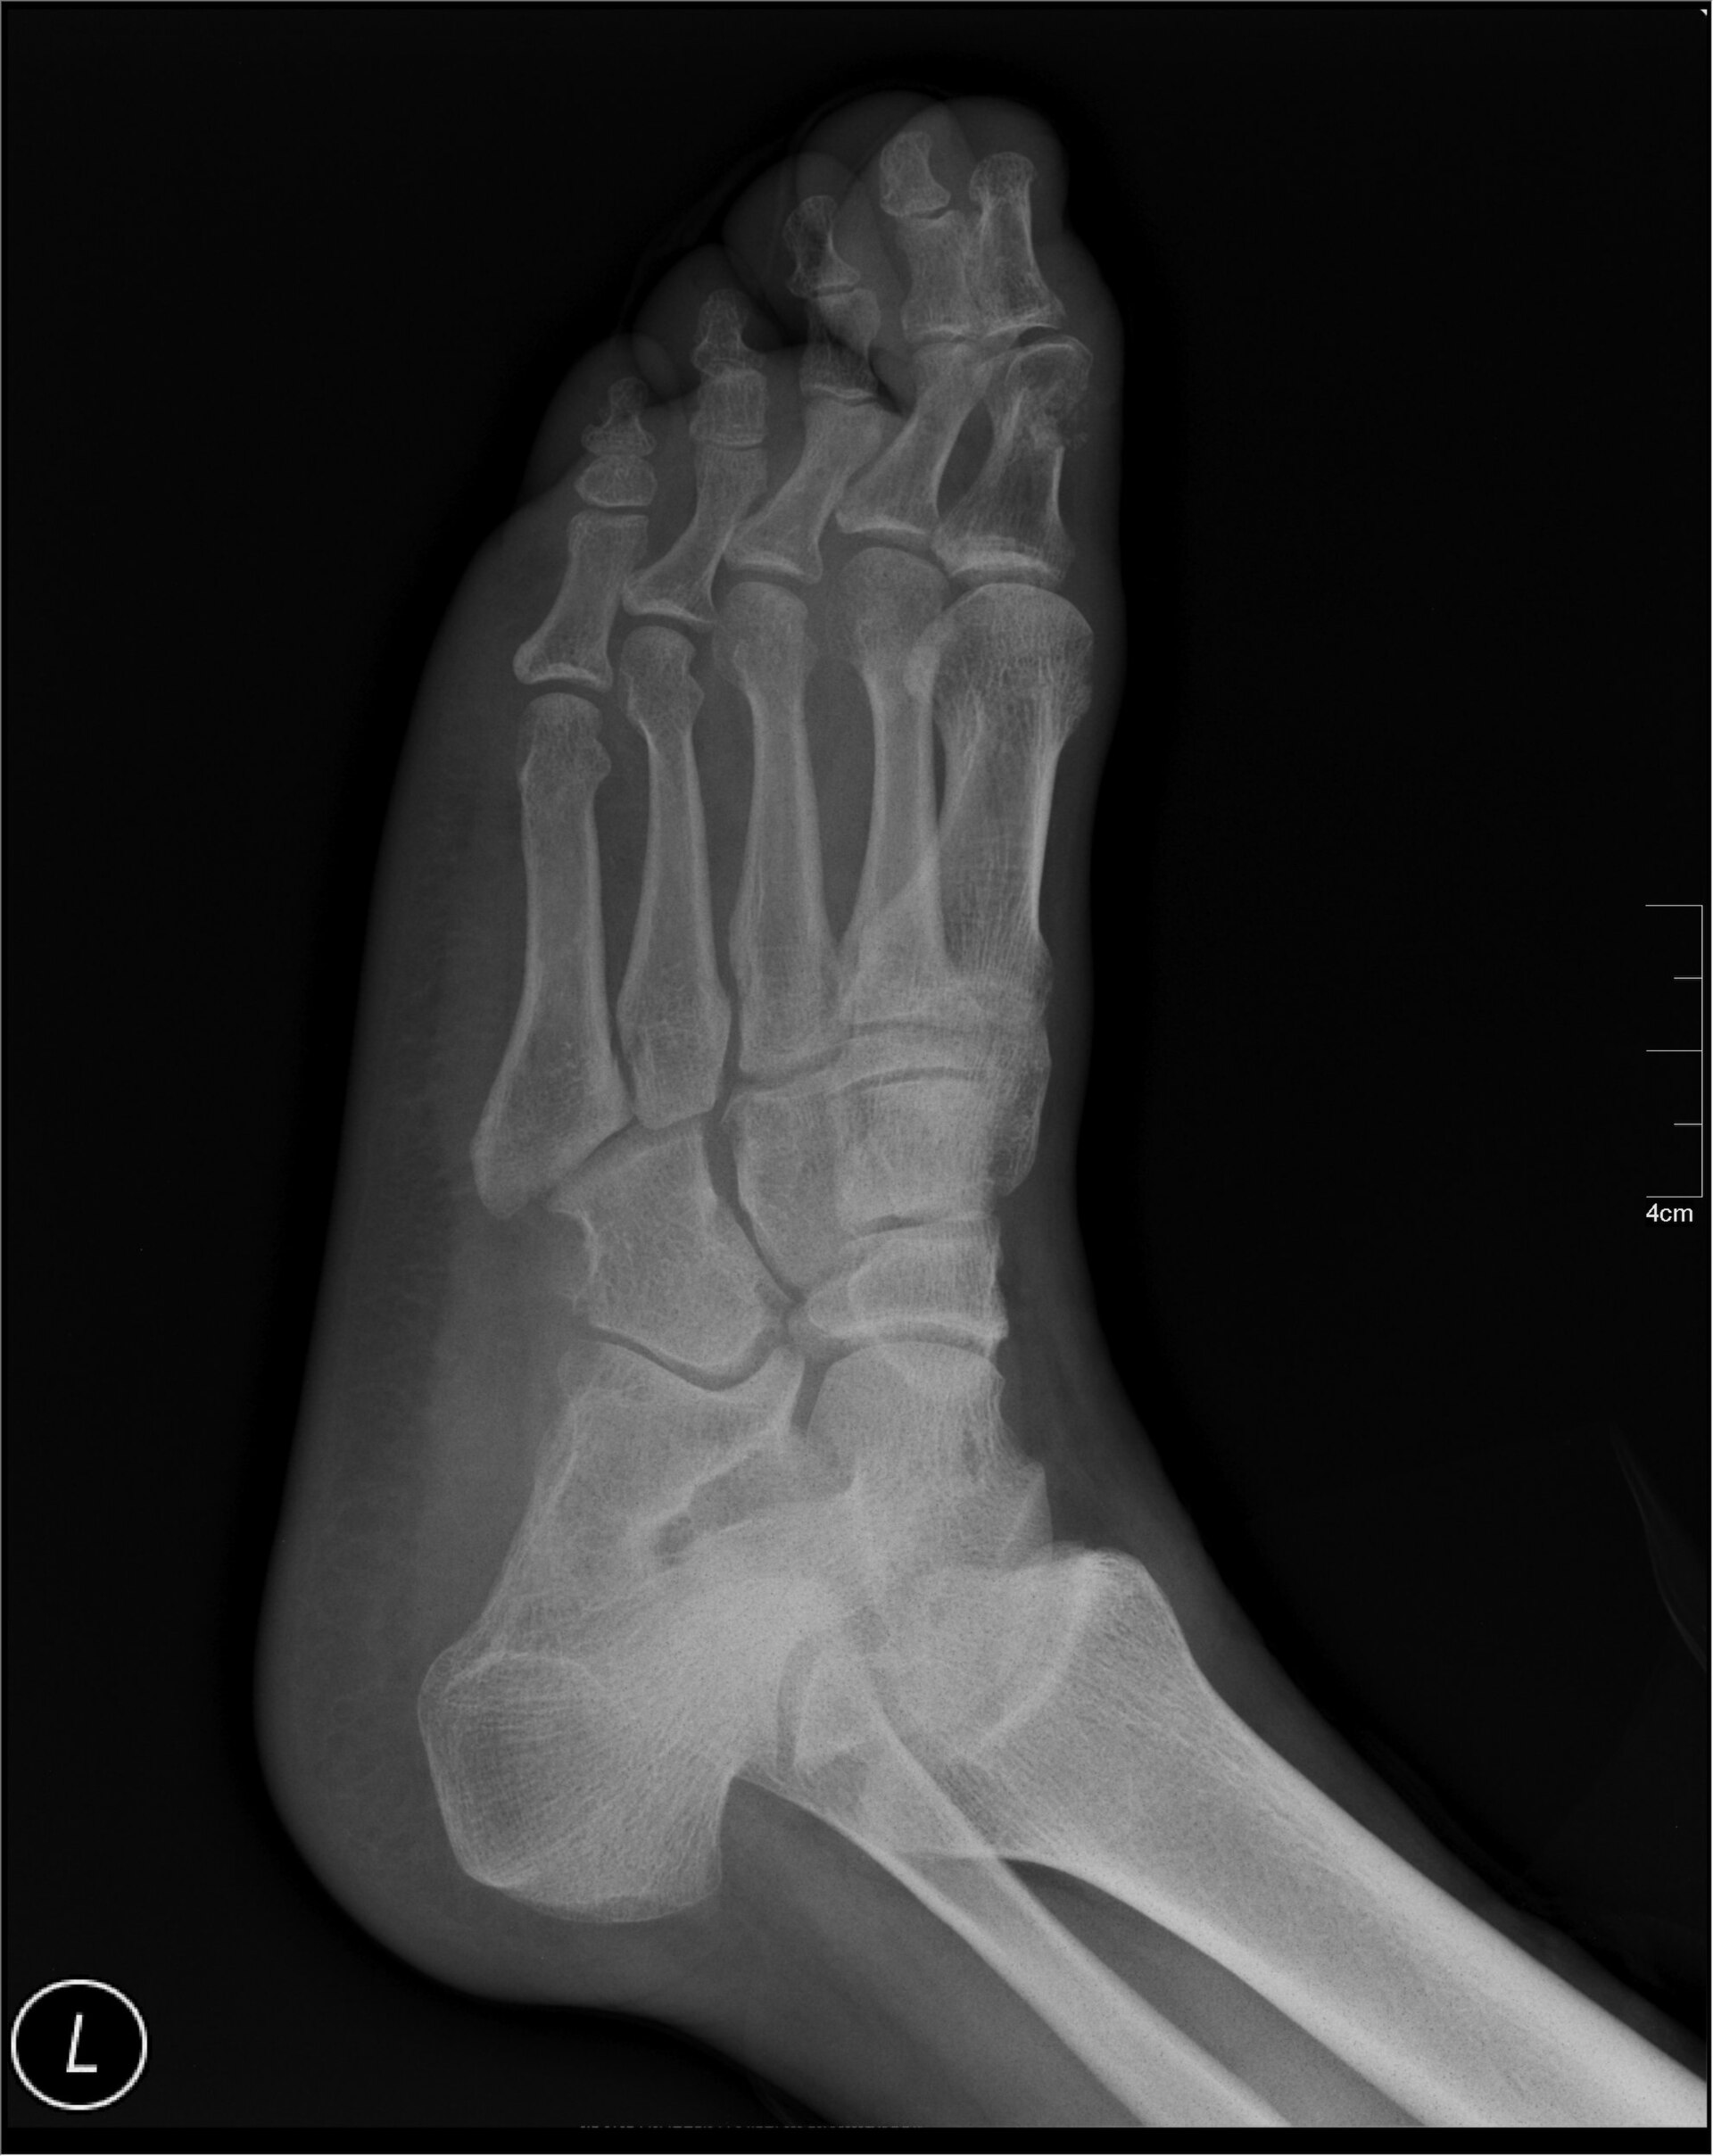

Plain radiograph of a human foot showing tarsal, metatarsal, and phalangeal bones.